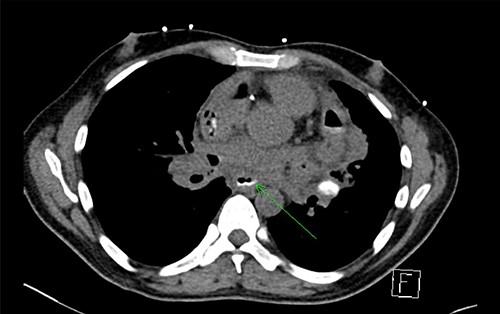

Initial chest X-ray demonstrated lucency over the left heart border and anterior mediastinum suggesting pneumopericardium (Fig. 1). A computed tomography (CT) scan of the chest demonstrated multiple pericardial collections containing loculated gas and fluid with calcification causing stenosis of the superior vena cava. An OPF was suspected (Fig. 2). Bilateral tree-in-bud nodularity reflecting active pulmonary infection with diffuse bronchitis and endobronchial plugging were also present.

CT with water-soluble oral contrast. Trace amount of contrast that extends to the left lateral aspect of the oesophagus representing a thin tract.